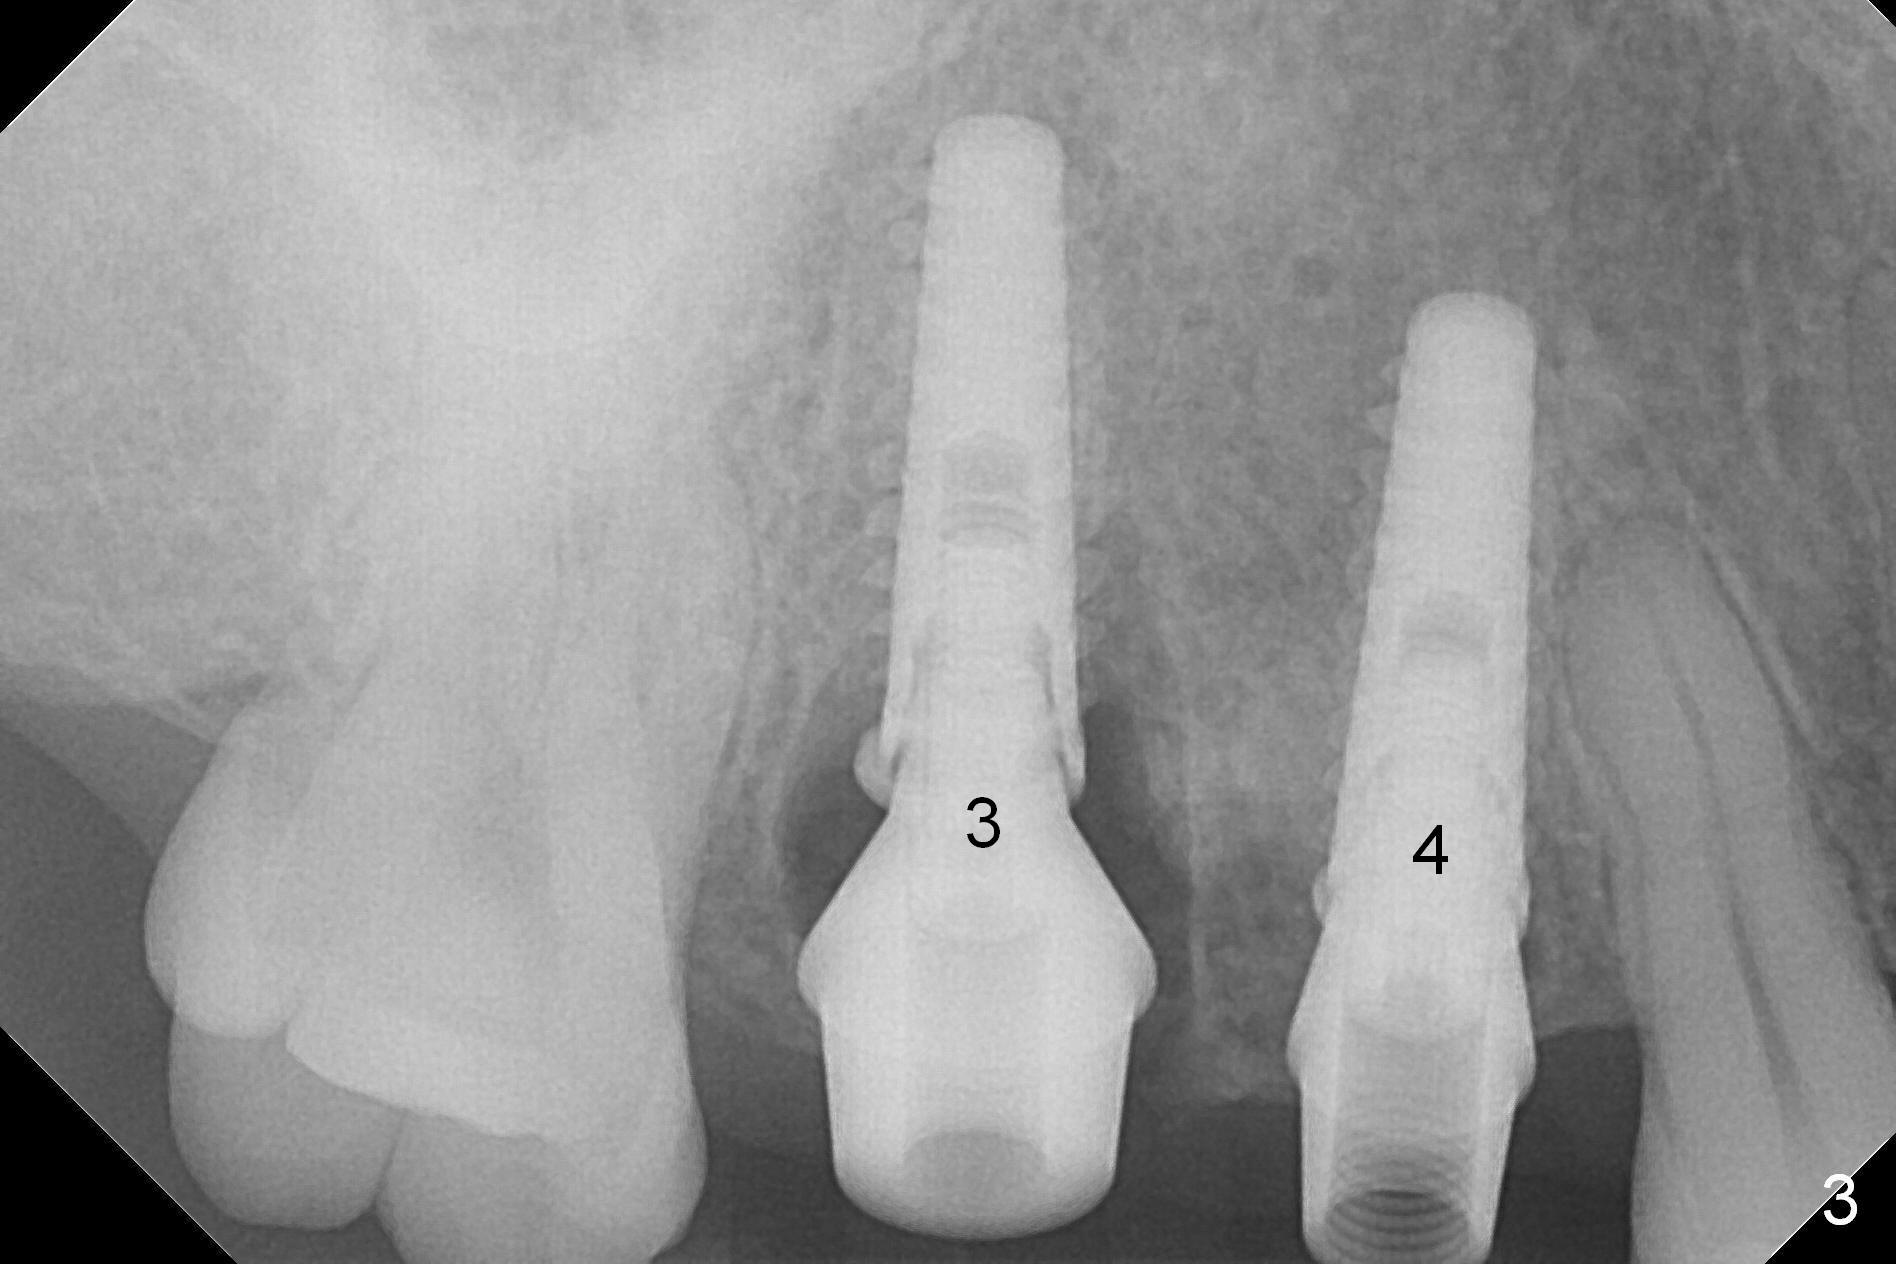

After extraction, osteotomy is established in the septum of #3 and the mesial slope of the shallow socket of #4 (Fig.2 red dashed line) for 11 and 13 mm deep, respectively. Since the septum is sloped palatally, a series of Magic Drills (MD) are used. A single large MD may wobble in the slope. By the time MD 3.8 mm is used, there is perforation palatally. The insertion torque of 4.5x13 mm IBS implant is less than 30 Ncm (Fig.3). In retrospectively, the osteotomy should have been initiated more buccally or deeper, since there is fair amount of clearance from the sinus floor (Fig.5 ^). The implant at #9 is 3.8x16 mm.

In contrast, osteotomy at #4 is finished with a single MD 3.3 mm. A 4x13 mm implant is placed with more than 50 Ncm. Pair abutments are immediately placed (6.5x4(3) and 4.5x4(3) mm) for splinted immediate provisional. The remaining socket (Fig.4 red dashed line) is filled with mixture of allograft, autogenous bone and Osteogen (*).